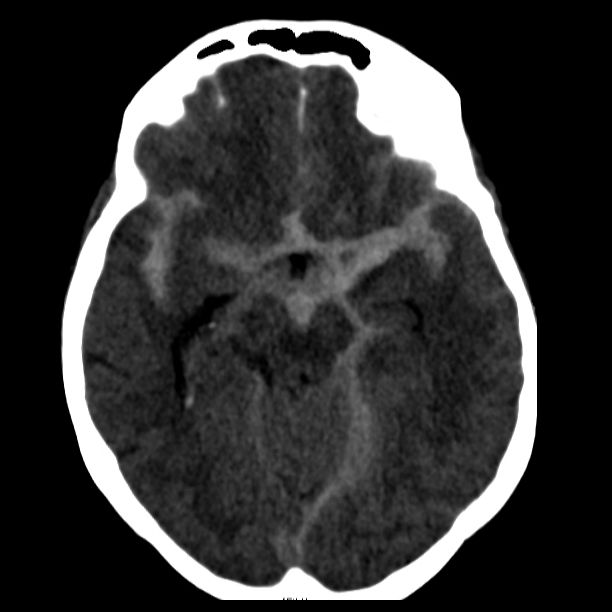

Als schnellste und sicherste Maßnahme gilt das craniale Computertomogramm (CCT). Hier lässt sich eine frische SAB meist zuverlässig darstellen, wobei auch bereits richtungsweisende Befunde, wie das Ausmaß der Blutung und eine eventuelle Lokalisation eines möglichen Aneurysmas bestimmt werden können. Darüber hinaus kann ein Angio-CCT, bei dem zusätzlich Kontrastmittel verabreicht wird und dann die intrazerebralen Blutgefäße gesondert rekonstruiert und dargestellt werden, weitere Informationen liefern. Der sogenannte “Goldstandard” zur Diagnose zerebraler Gefäßmissbildungen ist jedoch die zerebrale Angiographie. Dabei wird mit Hilfe eines speziellen Katheters über die Leisten- oder Armarterie Kontrastmittel gegeben und die zerebralen Blutgefäße hoch selektiv dargestellt. Sollten sich auf dem initialen CCT Zeichen des Hirnwasseraufstaus zeigen, der durch ein Verstopfen der Abflusskanäle durch das neu aufgetretene Blut bedingt ist, ist oft die Anlage einer Hirnwasserableitung nach außen notwendig (externe Ventrikeldrainage).

CT Bildgebung der klassischen subarachnoidalen Blutverteilung nach SAB

Als diagnostische Maßnahme wird in der Regel ein craniales Computertomogramm (CCT) durchgeführt. Intrazerebrale Blutungen lassen sich mit dieser Methode sicher diagnostizieren.